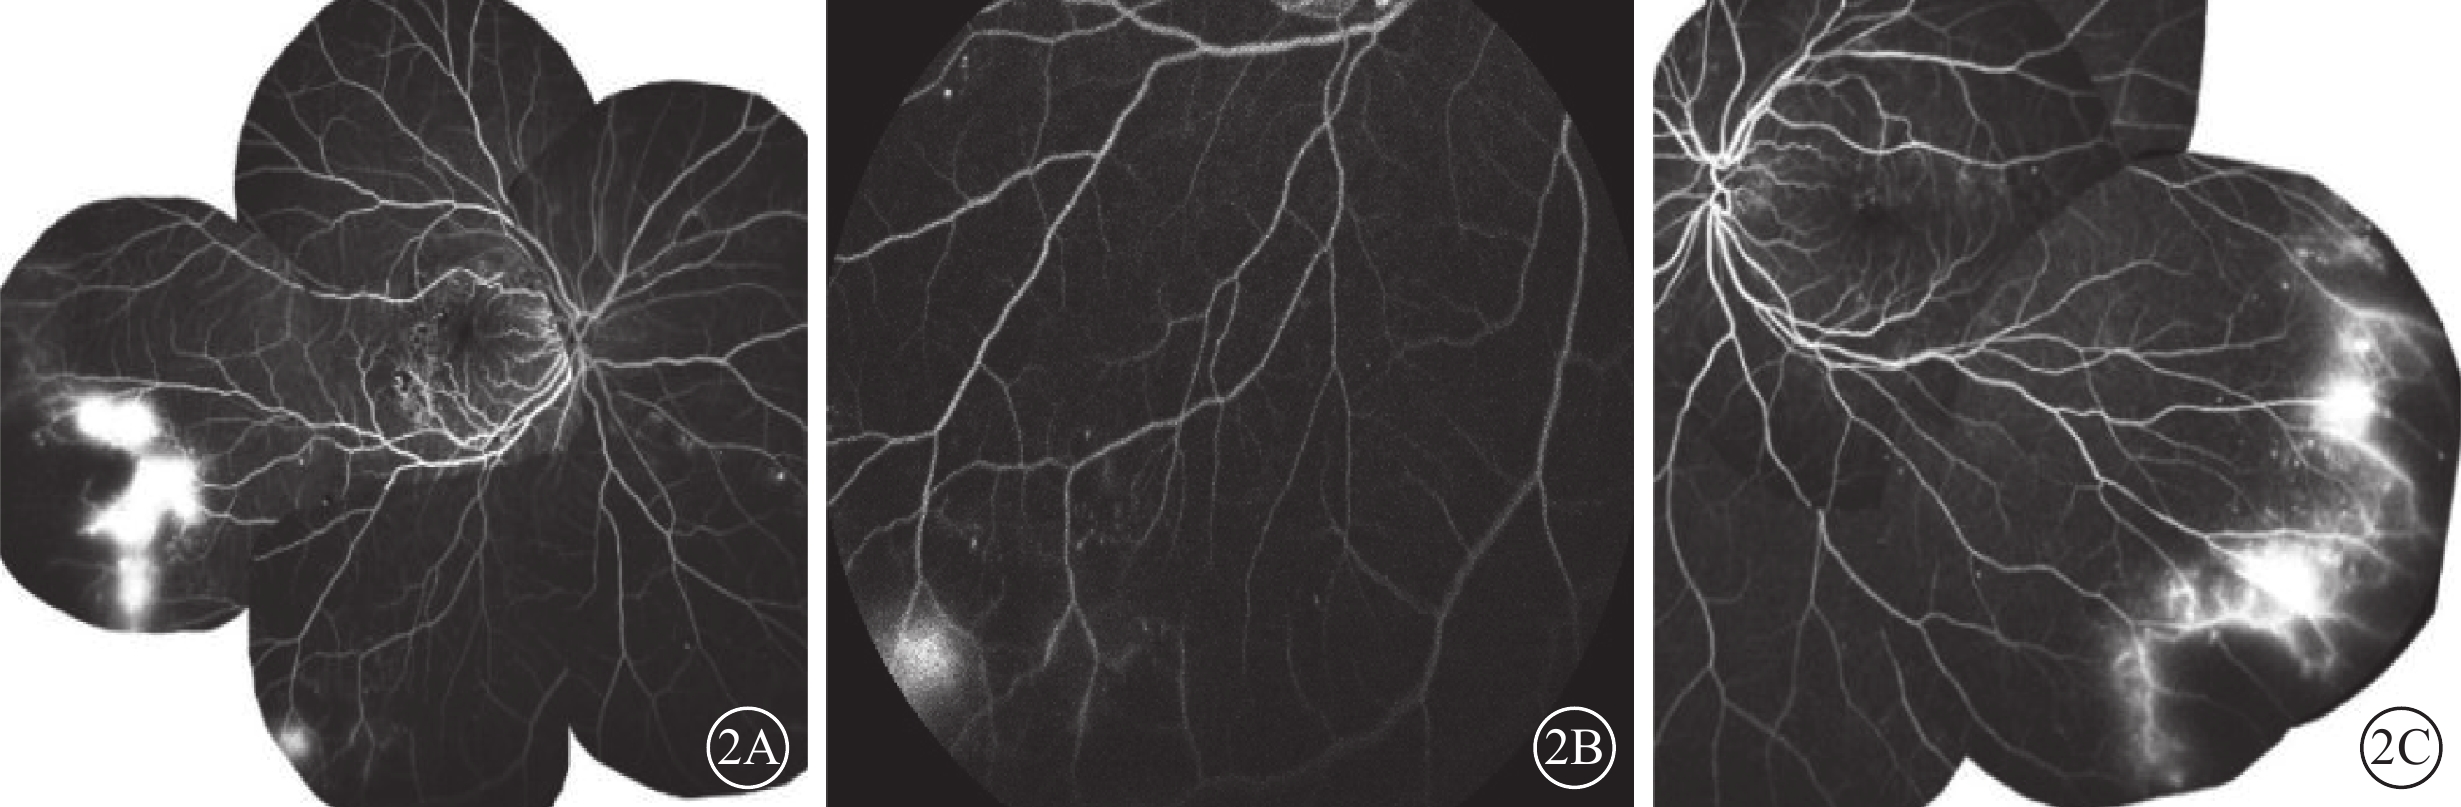

患者女,63歲。因雙眼視物模糊2年余、右眼為著,于2018年3月16日到中南大學湘雅二醫院眼科門診就診。患者既往身體健康,否認高血壓、糖尿病及長期服藥史等相關病史,家族史無特殊。眼科檢查:右眼視力0.1,矯正視力0.4;左眼視力0.3,矯正視力0.8。右眼、左眼眼壓分別為15、16 mm Hg(1 mm Hg=0.133 kPa)。雙眼眼前節未見明顯異常。左眼玻璃體腔可見均勻分布的星狀小體。眼底檢查,雙眼眼底可見微動脈瘤、出血及硬性滲出。右眼黃斑區顳側可見視網膜內出血,黃斑區視網膜水腫伴黃白色硬性滲出,顳側周邊視網膜可見一粉紅色鮭斑出血(圖1A);左眼黃斑顳上方可見一大動脈瘤,其周圍有黃色滲出(圖1B)。光相干斷層掃描檢查,右眼黃斑區可見視網膜增厚伴囊樣水腫,外叢狀層和外核層可見強反射點。熒光素眼底血管造影(FFA)檢查,雙眼視網膜均可見散在微動脈瘤點狀強熒光;右眼黃斑顳側可見小片無灌注區,顳下方周邊視網膜可見無灌注區與正常視網膜灌注區之間新生血管熒光素滲漏,與眼底鮭斑出血病灶對應處可見熒光遮蔽(圖2A,2B);左眼顳下方周邊視網膜可見與右眼類似的無灌注區以及熒光素滲漏(圖2C)。進一步實驗室檢查,空腹血糖8.04 mmol/L,糖化血紅蛋白7.3%。凝血酶原時間14.3 s(正常值10.0~14.0 s),血紅蛋白107 g/L(正常值115~150 g/L),紅細胞5.75×1012個/L(正常值3.80~5.10×1012個/L),紅細胞平均體積64.2 fL(正常值82.0~100.0 fL),紅細胞平均血紅蛋白含量18.6 Pg(27.0~34.0 Pg),紅細胞平均血紅蛋白濃度290 g/L(正常值316~354 g/L)。血液涂片提示為小細胞低色素貧血。血紅蛋白電泳:HbF 0.6%(正常值0.0%~2.0%),HbA2 5.5%(正常值1.8%~3.5%)。鐵蛋白299.51 ng/ml(正常值4.63~204.00 ng/ml),基因分析顯示其α珠蛋白正常,但β珠蛋白發生了CD17(A->T)基因突變(圖3)。結合內分泌科、血液科會診結果,臨床診斷:輕型β地中海貧血合并糖尿病視網膜病變(DR)。給予患者控制血糖及貧血治療;同時右眼行局部激光光凝及黃斑格柵樣激光光凝,左眼行周邊視網膜無灌注區激光光凝治療。隨訪3年,患者雙眼視力穩定。